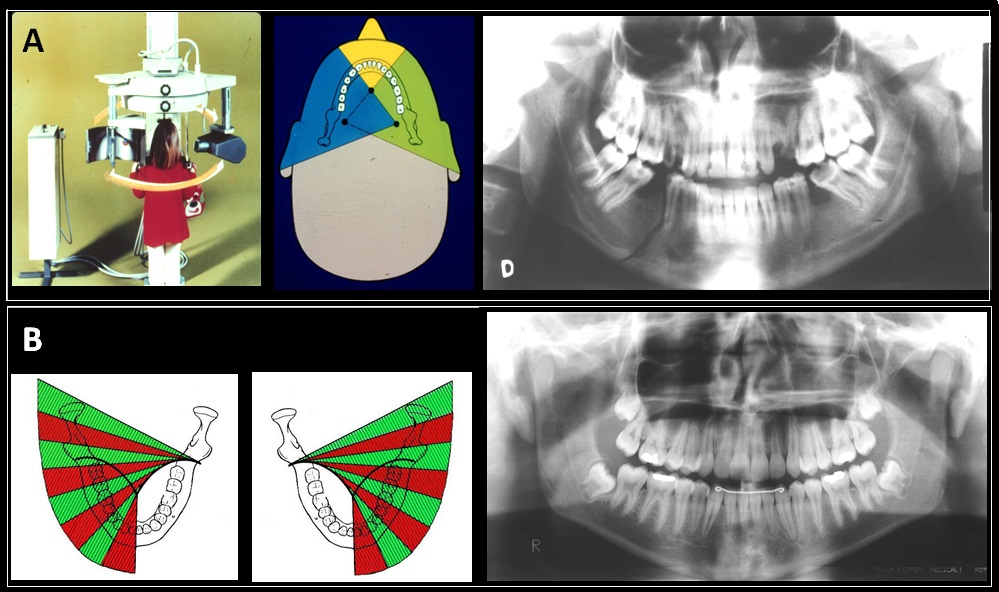

Ortodonticamente, podemos adotar 2 caminhos terapêuticos: o fechamento de espaço, por meio da mesialização dos dentes posteriores, ou a abertura de espaço, mantendo ou criando espaço para futura reabilitação protética, geralmente com implantes osseointegrados. Porém, a inserção de implantes osseointegrados requer que o paciente já tenha finalizado o crescimento ósseo. Em consequência, uma vez optado pela segunda abordagem. após o tratamento ortodôntico, precisamos preservar o espaço obtido através de próteses removíveis, próteses fixas ou, como sugerido mais recentemente, através de reabilitação com mini-implante ortodôntico e coroa estética (ROSA, 2022).

Entretanto, existe controvérsia em relação à inserção do mini-implante em áreas edêntula, pois, para uns, o mini-implante tem a capacidade de contribuir com a manutenção do osso alveolar na região edêntula (COPE, 2014), mas para outros, o osso alveolar perfurado pelo mini-implante não acompanha o crescimento vertical ósseo (KOKICH, 2011).